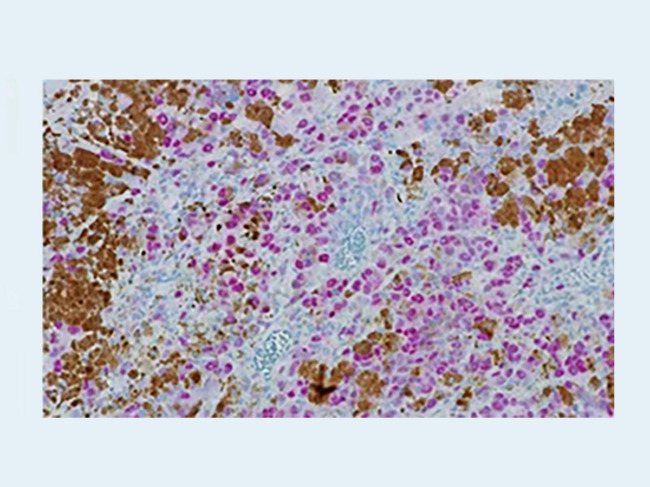

Anti-PRAME - rabbit monoclonal primary antibody - Roche Diagnostics

Roche’s anti-PRAME antibody launched in China for melanoma diagnosis

China’s NMPA gave the nod to Roche Diagnostics (Shanghai) Ltd.’s anti-preferentially expressed antigen in melanoma (PRAME) (EPR 20330) that could help to speed up melanoma diagnosis and improve survival rates. Read More